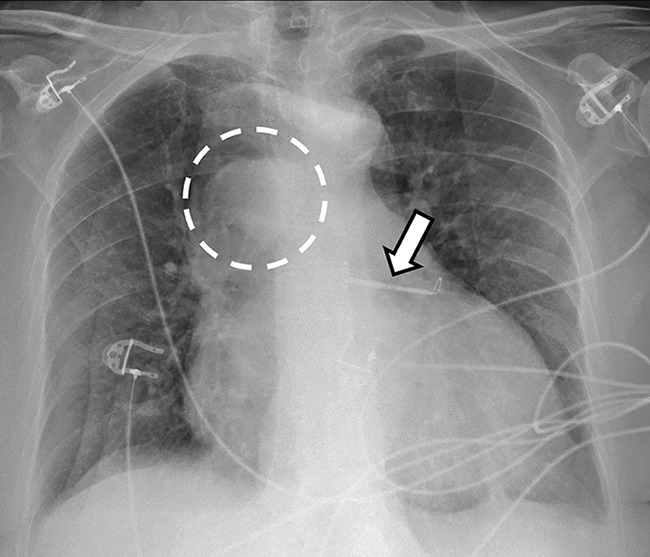

Abstract Image